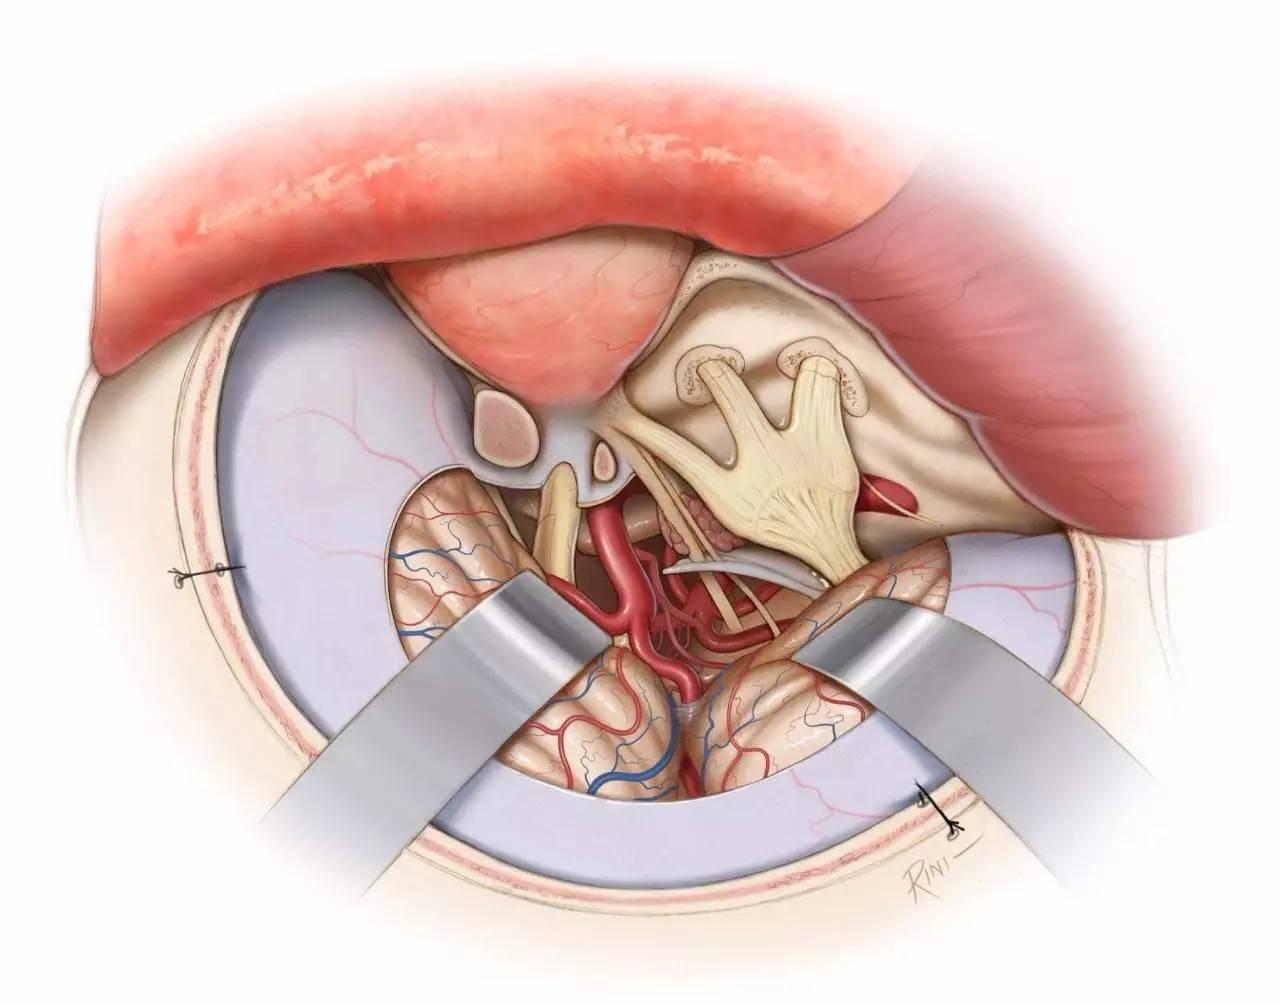

图2:逐层分步解剖右侧海绵窦。海绵窦外侧壁内走行有动眼神经、滑车神经、三叉神经眼支和上颌支(Rhoton教授原图认为上颌支位于海绵窦以外,译者注),外展神经则紧贴颈内动脉行于海绵窦内部(左上图)。剥开覆盖颞叶的外层脑膜层(即海绵窦外侧壁的外层,译者注),可见动眼神经和滑车神经进入海绵窦顶壁,并前行进入眶上裂(右上图)。动眼神经在海绵窦顶壁行于一小段蛛网膜池中(红色箭头),直至前床突下缘时才进入海绵窦侧壁(黄色箭头,左中图)。剥除海绵窦外侧壁的残余硬膜(外侧壁的内层,译者注)(右中图)。三叉神经后根已被翻向前方,以显露海绵窦下界的后部(黄色箭头),位于岩尖三叉神经压迹的内侧(左下图)。向前翻开三叉神经主干及全部三分支,显露海绵窦的静脉间隙(右下图)。(感谢Rhoton教授对图片的授权)

图3:硬膜外入路行右侧海绵窦的手术学解剖。颞前-眶颧开颅及硬膜外前床突切除术已完成,眶上裂的外侧缘已显露(左上图,此时硬膜外前床突切除术其实尚未完成,译者注)。在眶上裂的外侧缘处切断额颞或脑膜眶硬膜返折,将海绵窦外侧壁的外层从内层上剥离。因此,掀开海绵窦外侧壁的外层(脑膜层),即可显露融入外侧壁内层的颅神经(右上图)。

切断脑膜中动脉,继续向后内侧剥离硬膜,即可暴露岩浅大神经,其通常行于岩骨段颈内动脉上方,故可作为其定位标志。沿中颅窝剥离硬膜的内侧界为前岩床突硬膜返折,后界为岩骨嵴(左中图)。床突旁区域的放大观(右中图)。注意,经Parkinson三角进入硬膜内是可能的(译者认为是“海绵窦内、硬膜间”,译者注)。进一步剥除海绵窦外侧壁的内层(左下图)。病灶经外侧壁侵犯海绵窦的通道也即为手术进入海绵窦的径路。此时可见以下中颅窝三角:前内侧三角(三叉神经眼支和上颌支之间)、前外侧三角(三叉神经上颌支和下颌支之间)、后外侧三角(即Glasscock三角,三叉神经下颌支和岩浅大神经之间)、后内侧三角(即Kawase三角,三叉神经下颌支外侧与岩浅大神经后方区域)。最后一图展示了去除中颅窝底和内听道顶壁部分骨质后的解剖(右下图)。(感谢Rhoton教授对图片的授权)

图4:海绵窦区的硬膜内入路解剖。大型肿瘤应联合硬膜内及硬膜外入路。(感谢Rhoton教授对图片的授权)

图7:显示了海绵窦的各个外科三角。肿瘤的生长方式常常决定了术中进入海绵窦的路径。在对神经移位方式进行预判后,滑车下三角和滑车上三角常可作为合适的入口。中颅窝前内侧、前外侧三角也常常需要被打开。注意Glasscock三角的位置,其用于颈内动脉岩骨段的暴露。